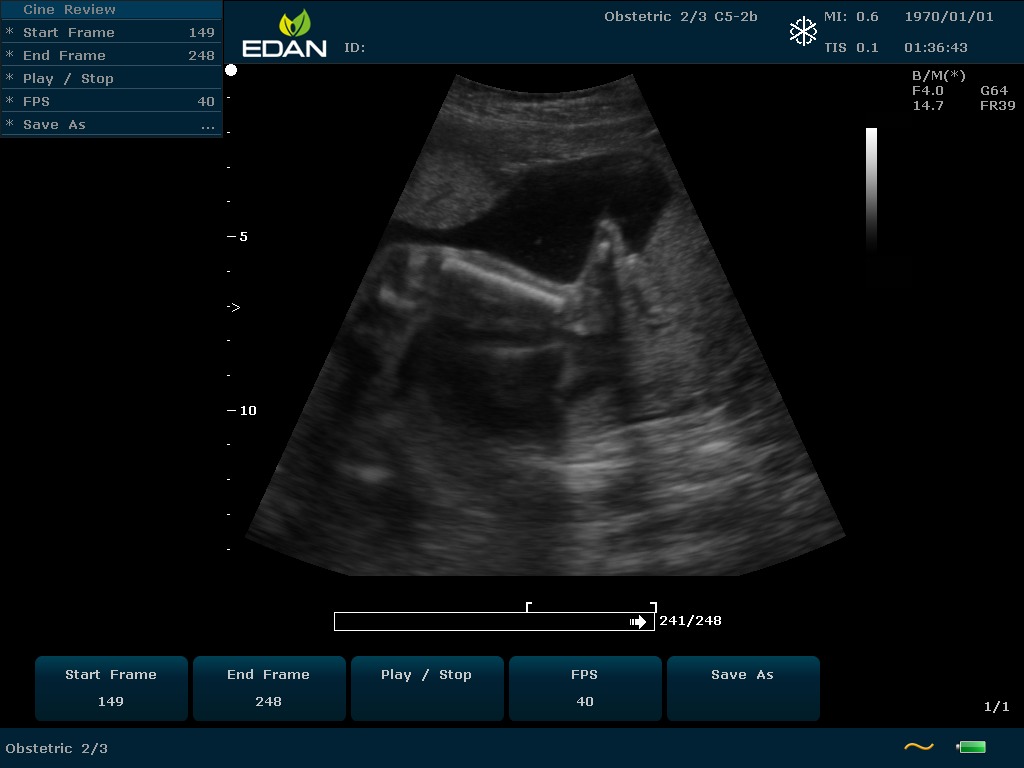

Особенность U60 Edan — расширенное применение. Ультразвуковой аппарат рекомендован для абдоминальных исследований, гинекологии и акушерства, кардиологии, педиатрии, урологии, изучения малых органов, сосудов. Для U60 Edan используются конвексные, линейные, фазированные и внутриполостные датчики.

Передовые технологии позволяют повысить качество визуализации в несколько раз. УЗИ-аппарат U60 Edan отличается возможностью быстрой настройки визуализации. Специальные функции позволяют моментально отображать данные за счет быстрой оптимизации параметров. Режимы визуализации: B-mode, M-mode, Color Doppler, Power Doppler Imaging, Pulsed Wave Doppler, Continuous Doppler.